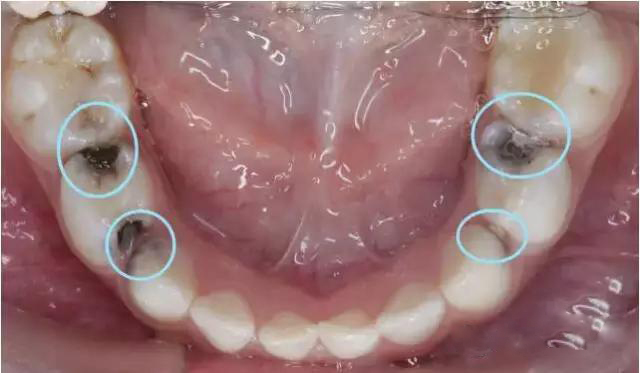

1.当孩子的第一尖牙,第二尖牙出现龋洞一定要去看牙医,因为这几颗牙齿在孩子12-13岁才会脱落,由于孩子的牙齿髓腔大,龋齿发展迅速,等到发现的时候不得不打麻药抽神经

3.乳牙还没有自动脱落,恒牙就长出来了,而且恒牙是从乳牙的内侧长出,形成了“双层牙”。这时,家长要尽早带孩子去医院拔除滞留的乳牙,免得令牙齿排列不整、咬合不正。如果上颌门牙缝隙过大、畸形牙齿从上门牙位置长出、一颗门牙从异常位置长出,这说明可能有一个地方长多颗牙齿的情况,也要到医院就诊。